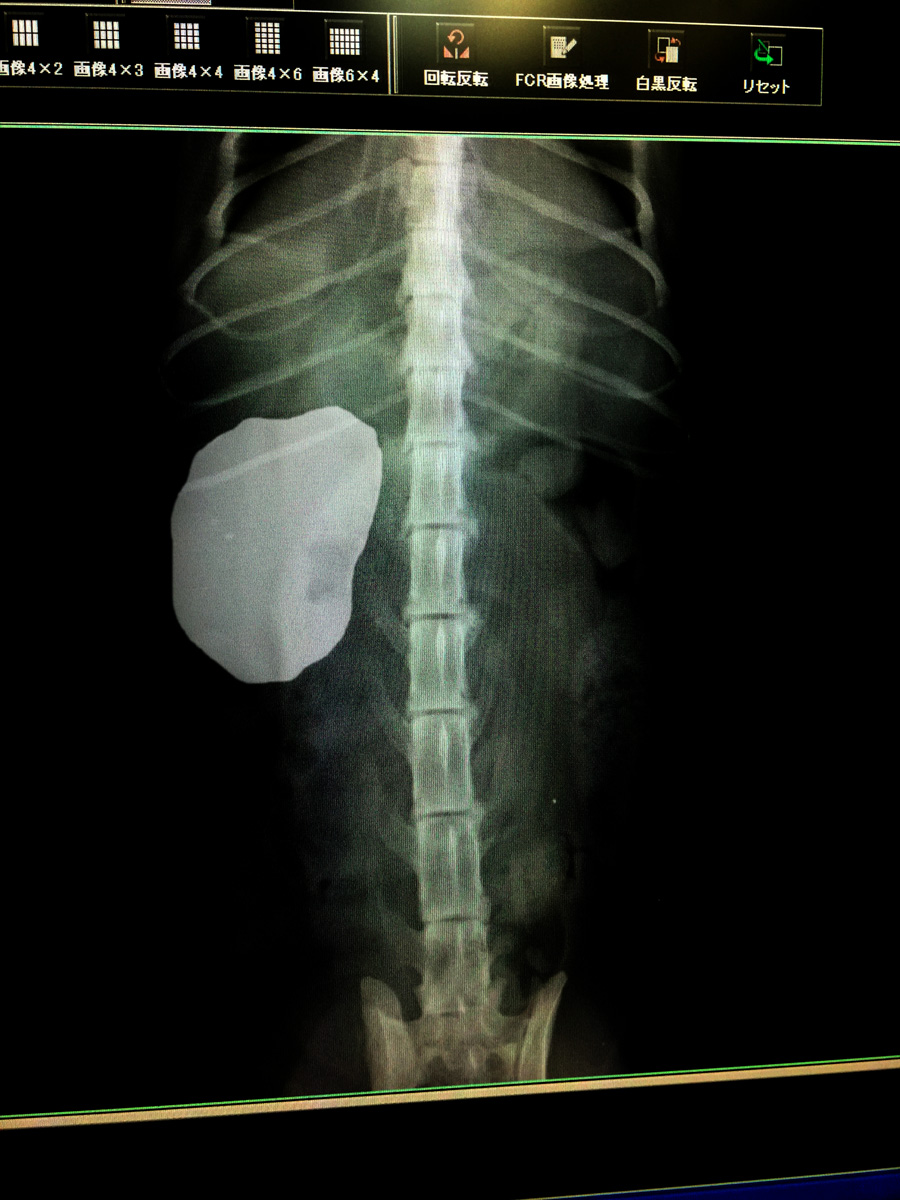

うおっほ、これがだいずさんのレントゲン写真です

これがだいずさんの右の腎臓です

いや全く無い訳ではありませんが3年前の写真と比べると明らかに左側が萎縮してます

その代わり動いている右側が肥大してフル稼働しているようです

だいずさんは生まれ付き左側の腎臓が機能不全と考えられます

8. 肋骨細ー

てっきり背中から撮ったレントゲン写真だと思いましたが、

左に見えるのが右の腎臓と書いてある以上、腹ばいにされている、

だいずさんの姿が浮かびました。哀れじゃのー